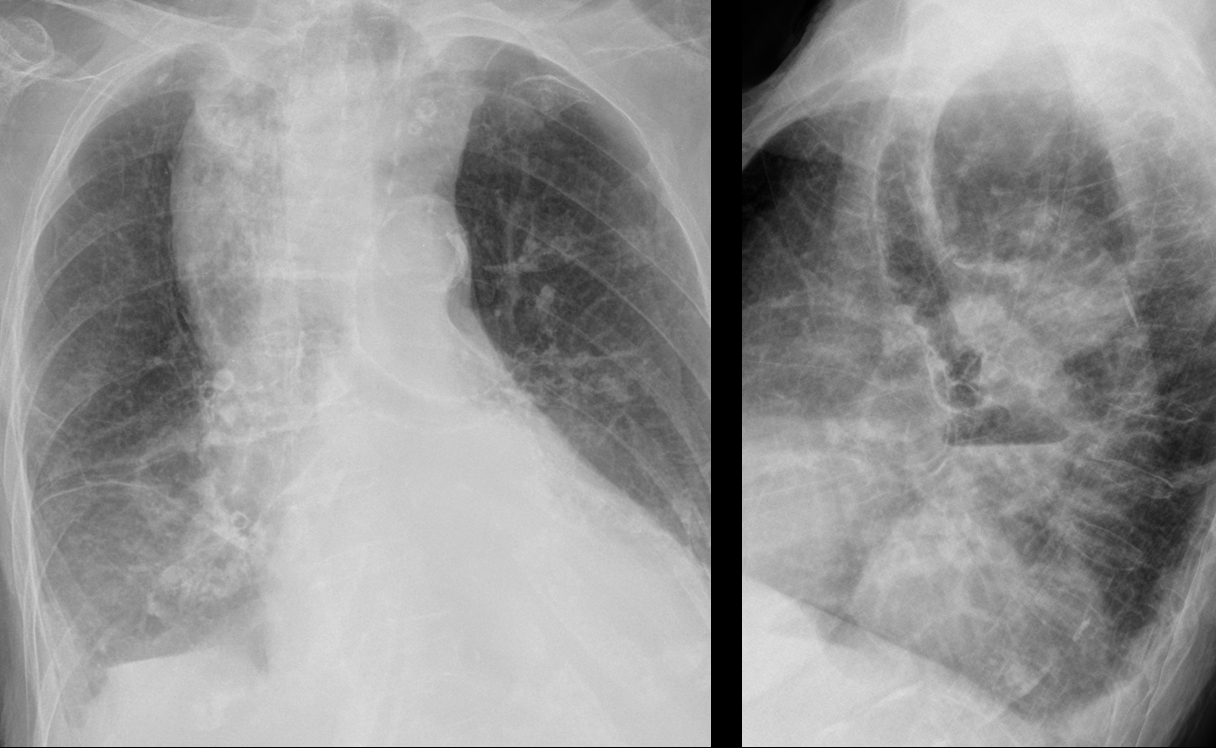

Dilated esophagus- Pa and lat from different dates

Mediastinum

Miscellaneous